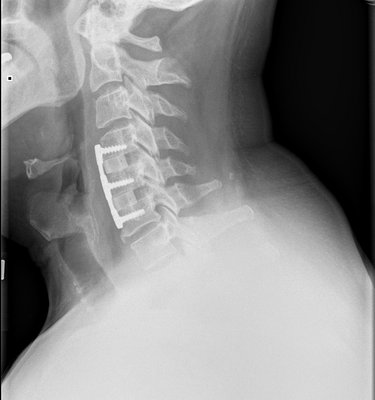

Saw my surgeon today with fresh X-rays. (below)

He likes how it is looking, wants to see me again in three months, at which time we'll discuss my return to flying. Thus grounded for the summer, I'll have to miss Hyner this weekend and July 4th.

My fusing plugs and titanium shield.

Front View

Wow, Cragin, those are some impressive x-rays. Hope you can make it out to Hyner for Labor Day.